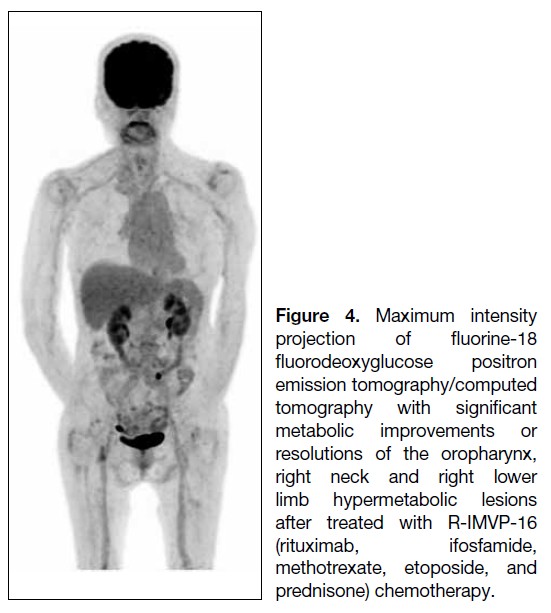

The patient subsequently received six cycles of

R-IMVP-16 (rituximab, ifosfamide, methotrexate,

etoposide, and prednisone) over 5 months. End-of-treatment 18F-FDG PET/CT showed metabolic

resolution of the right tonsillar/oropharyngeal mass and

other infiltrative perineural lesions in the neck region

and right lower limb, indicating a favourable treatment

response (Figure 4). Clinically, her numbness subsided,

with improved sensation in the previously affected

regions and right lower limb power improved to 4 out

of 5, consistent with the 18F-FDG PET/CT findings.

Both clinical and imaging findings favoured a positive

treatment response of the perineural and muscular

lymphomatous involvement in this patient with recurrent

lymphoma.

Figure 4. Maximum intensity

projection of fluorine-18

fluorodeoxyglucose positron

emission tomography/computed

tomography with significant

metabolic improvements or

resolutions of the oropharynx,

right neck and right lower

limb hypermetabolic lesions

after treated with R-IMVP-16

(rituximab, ifosfamide,

methotrexate, etoposide, and

prednisone) chemotherapy.